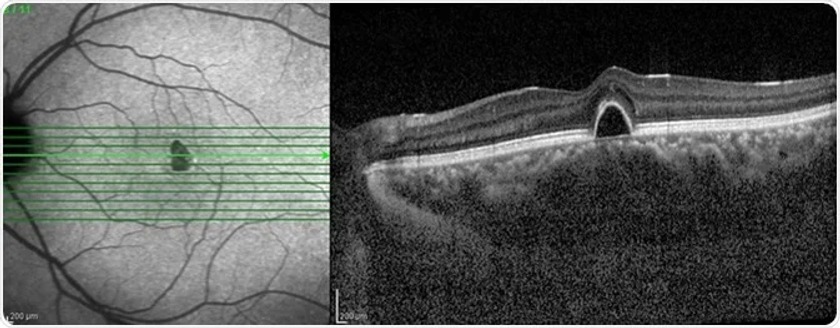

1.Optical Coherence Tomography (OCT) & OCT-Angiography:

This non-invasive imaging technique uses light waves to create cross-sectional images of the retina, optic nerve head, and other structures at a microscopic level, aiding in the assessment of conditions like optic neuritis, optic nerve atrophy, and other neuro-ophthalmic disorders. Additionally, OCT angiography helps in diagnosing and monitoring ischemic optic neuropathy that occurs in diabetic and hypertensive patients.

Diagnosis:

Imaging Tests: Optical coherence tomography (OCT) can help visualize the optic nerve and surrounding structures.